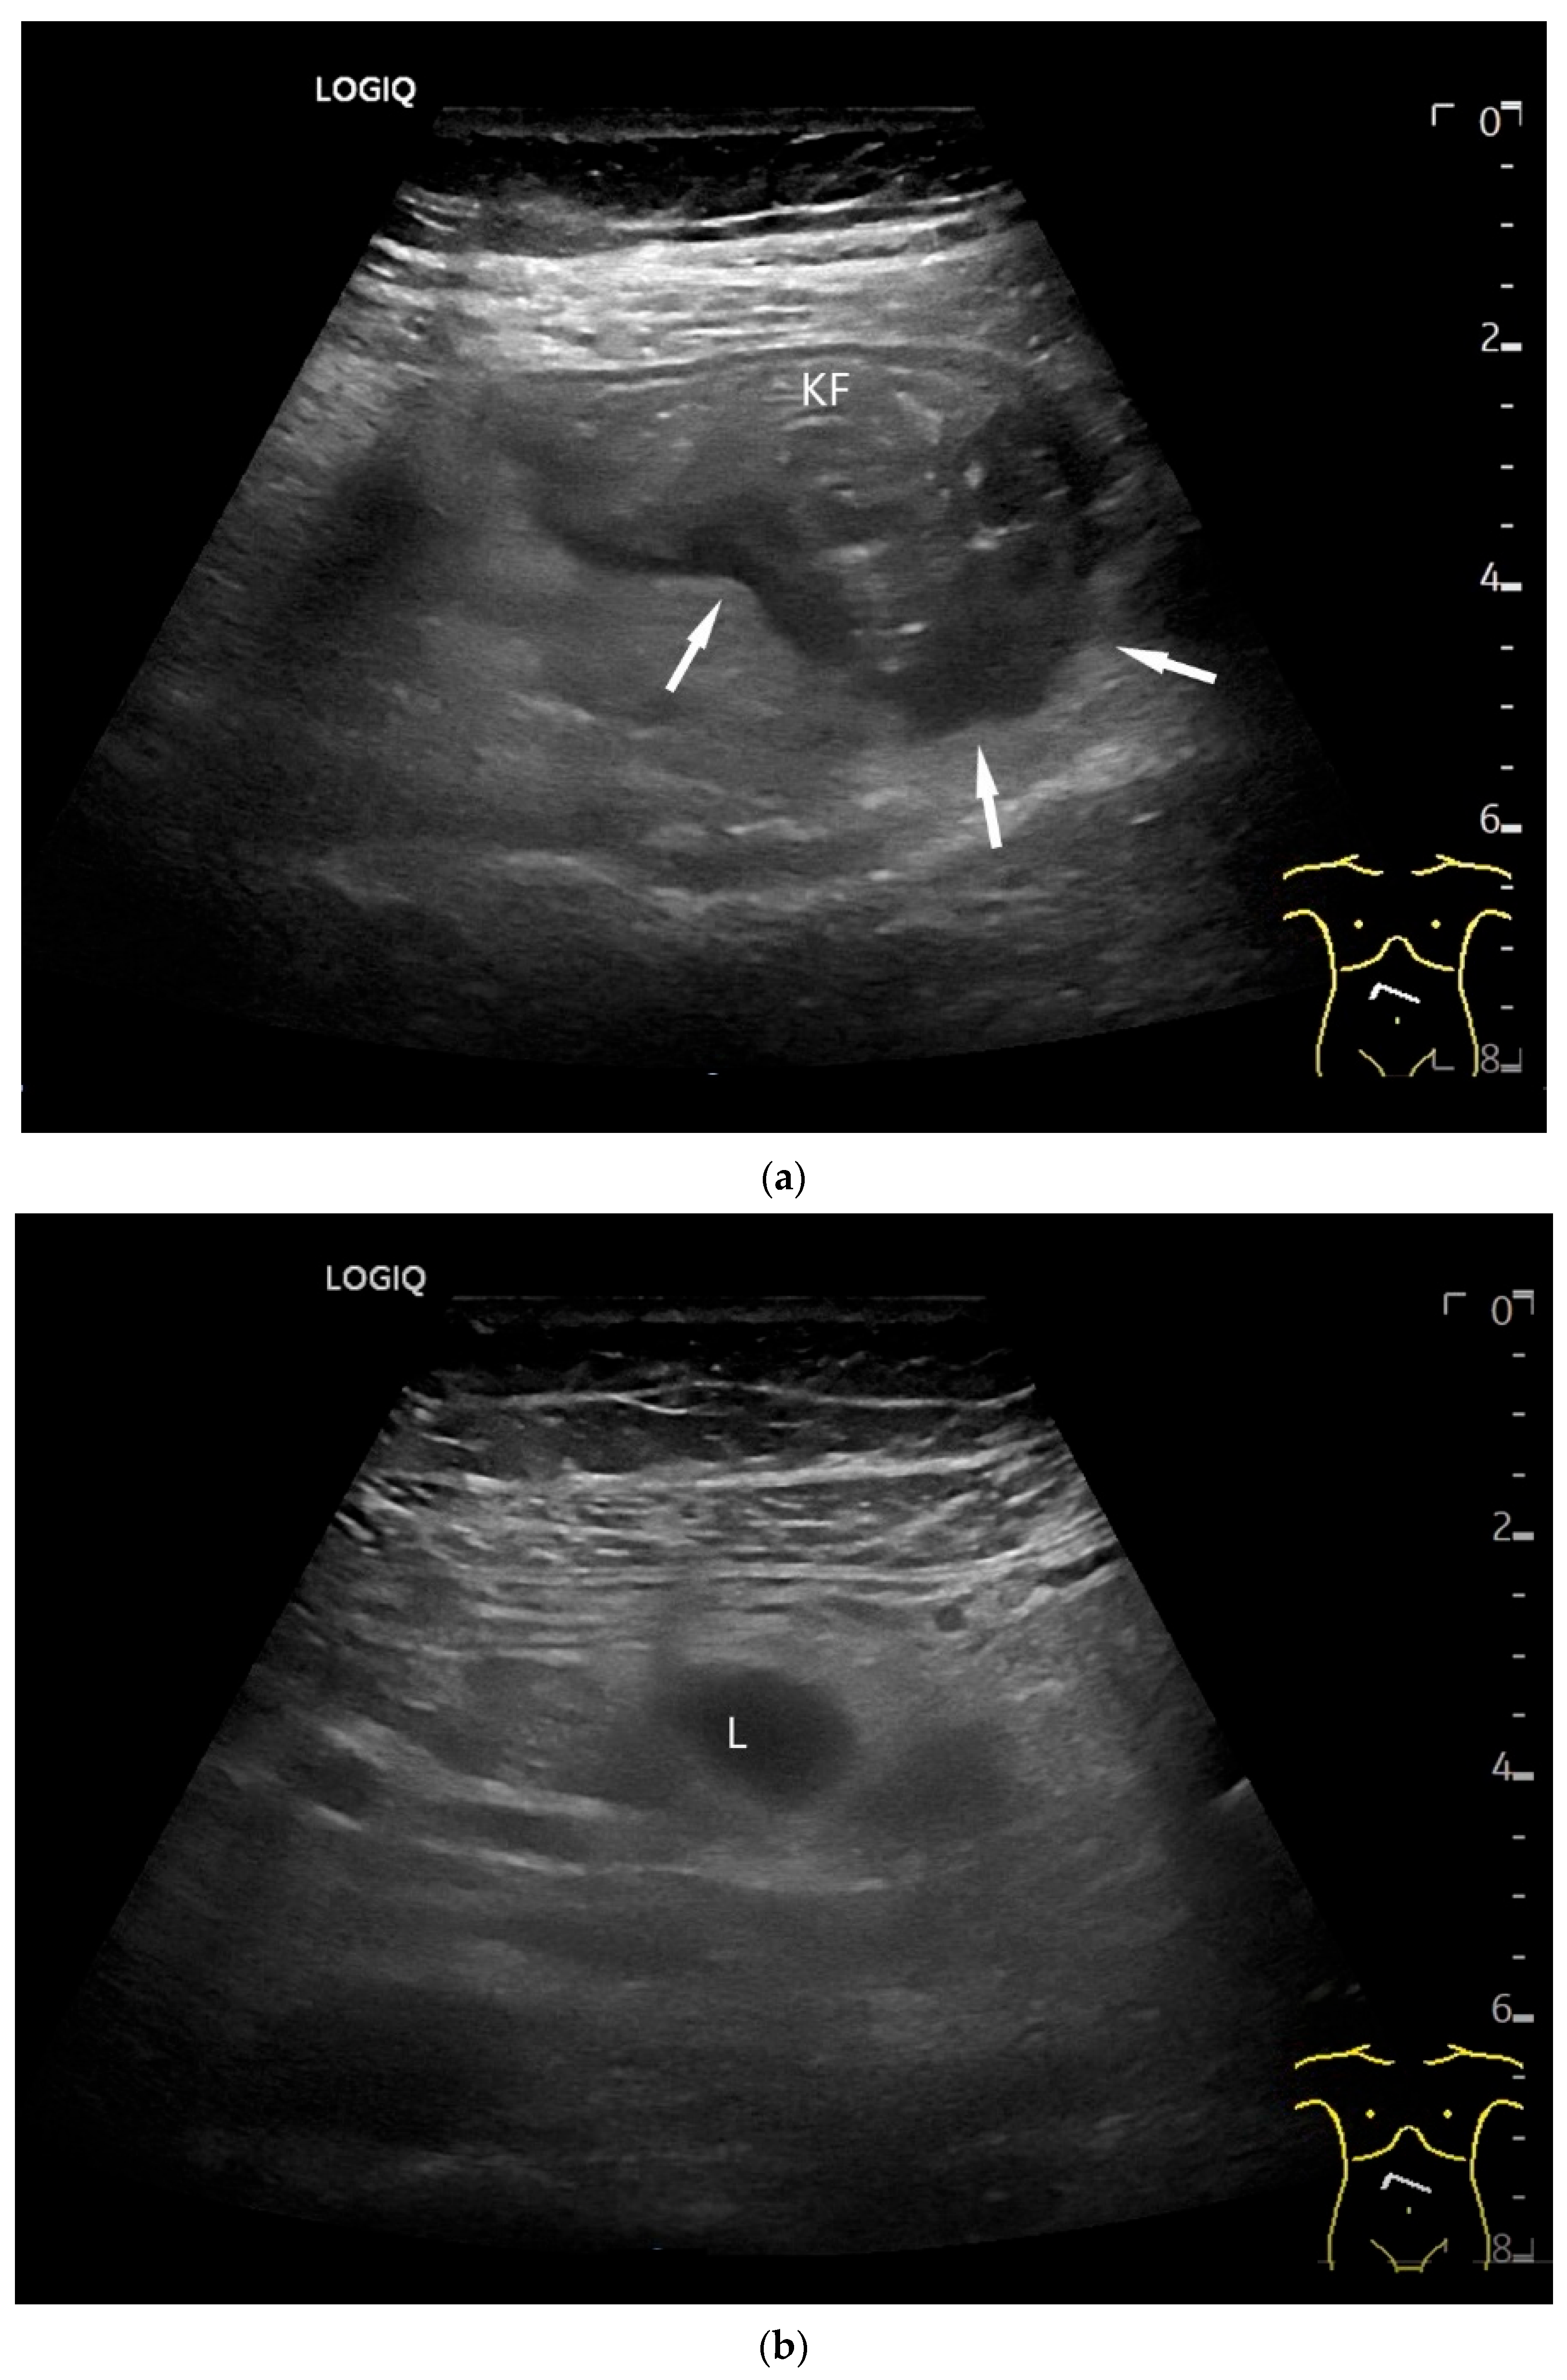

Figure 6.

Jejunal Adenocarcinoma. Segmental hypoechoic wall thickening (arrows) in the jejunum discovered during anemia diagnostics. Kerckring folds are faintly visible (KF) (a). Adjacent to this is a large round hypoechoic lymph node (L). The surrounding area shows hyperechoic changes (b).

Imaging: Tumors in the jejunum and ileum are usually circular ring-shaped and lumen-stenosing. In the duodenum, about one third have a polypoid component, but a proportion of cases show plaque-like growth [70]. On US, the adenocarcinoma presents as hypoechoic wall thickening with lumen narrowing. The infiltrative wall process may show further tongue-shaped hypoechoic infiltrations into the surrounding tissue. In the case of lymph node involvement, the mesenteric lymph nodes at the level of the tumor may be enlarged and/or morphologically conspicuous [71,72] (Figure 5 and Figure 6).